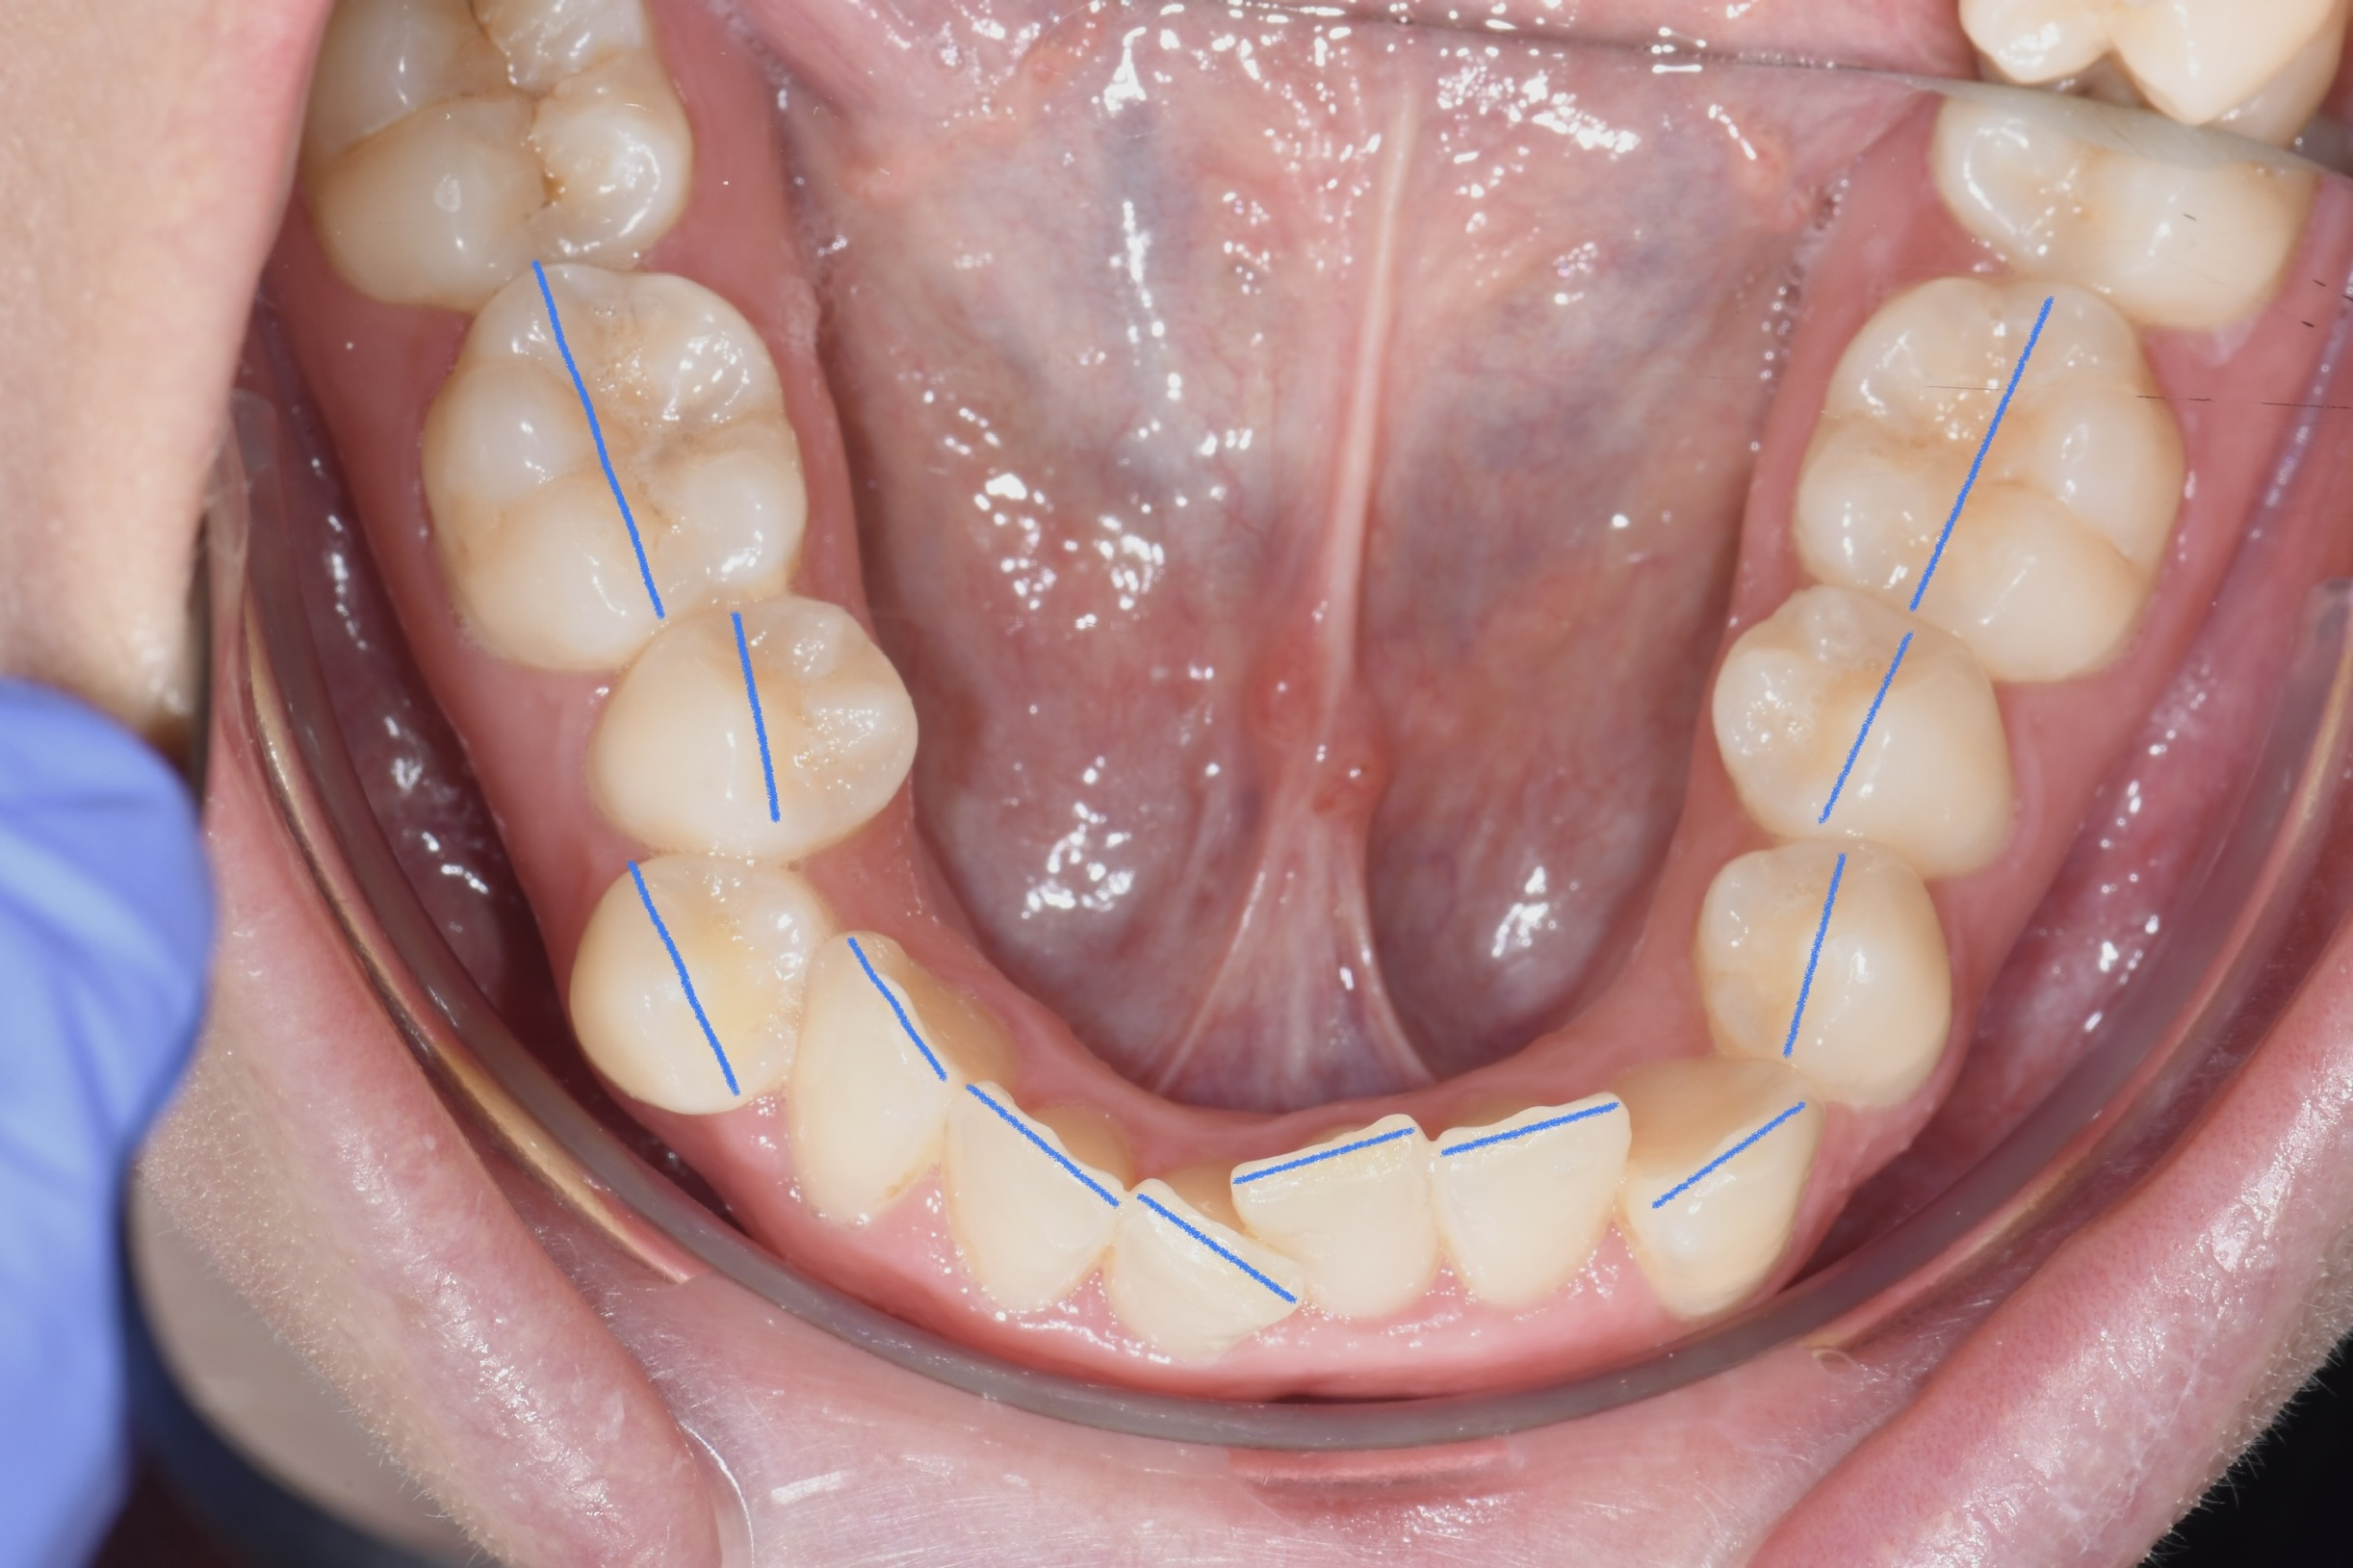

Az elmúlt évekből rengeteg szakmai referenciát tudnánk bemutatni, amelyek különböző fogszabályozási problémákat oldottak meg. Válogatva a több száz esetből, ezen az oldalon olyan képeket, információkat igyekeztünk bemutatni, amelyeknek a segítségével a jövőbeni pácienseinknek azt tudjuk üzenni: A Te fogsorod is lehet gyönyörű!

(Képeket a Pácienseink külön írásos beleegyezésével mutatjuk be!)